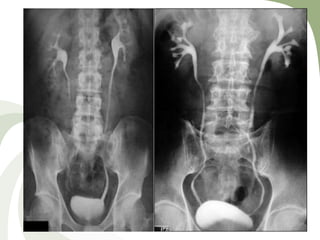

MCUG is the most diagnostic examination

– will show a heavily trabeculated bladder

– prominence of the bladder neck

– dilatation of the posterior urethra

– focal narrowing of the stream at the site of the valves

– Vesicoureteral reflux should be sought

Micturating cystourethrogram

1. Evaluation of structural and functional bladder outlet

obstruction

2. Evaluation of reflux

3. Evaluation of the urethra in males and females

4. Gold standard investigation for posterior urethral valve.

• #59 Marked dilatation and elongation of prostatic urethra (P), with reflux into prostatic ducts (straight arrow) secondary to posterior urethral valves (curved arrow) with bilateral vesicoureteral reflux into dilated ureters (U)